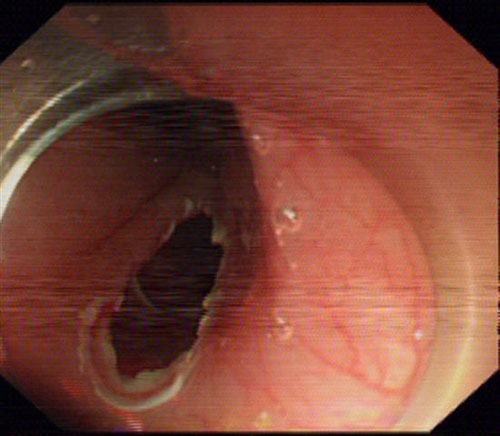

内镜见食管中段肿瘤